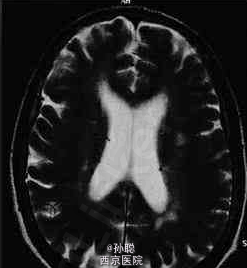

患者女性,31岁,教师,因有房屋旋转感和行走不稳2天就诊。房屋旋转感呈持续性,平卧时可部分缓解。这些症状使患者无法正常工作。发病无明显诱因,无其他不适,无恶心和头痛。自觉听力正常,无耳鸣。无其他神经系统症状的主诉。目前仅服用口服避孕药。患者在3个月前度假时用左眼照相有困难。该症状在1周内自发缓解,患者未寻找原因。最近,尤其是在穿衣服时右手发生轻度震颤,但由于患者是左利手,故未造成大碍。 体格检查:一般情况可。无发热,心血管检查正常。视诊耳道和鼓膜无异常,临床检测无听力受损表现。右眼视力6/6,左眼视力6/9。双侧瞳孔对称,左眼瞳孔传入缺陷。眼底镜检查示左眼视盘较右眼苍白。眼外肌运动检查发现,当看向右侧和垂直凝视时出现眼球震颤。眼球震颤与头位无关且不易疲劳。其他颅神经检查正常。肌力、肌张力和肢体反射均正常。但指鼻试验示右上肢呈意向性震颤,右手快速轮替运动较左手差。其他协调功能和感觉功能正常。 脑脊液(CSF)检查发现,CSF中IgG水平升高,IgG在电泳中分解成寡克隆带。脑脊液检查显示单核细胞计数和蛋白质中度升高,寡克隆带阳性。